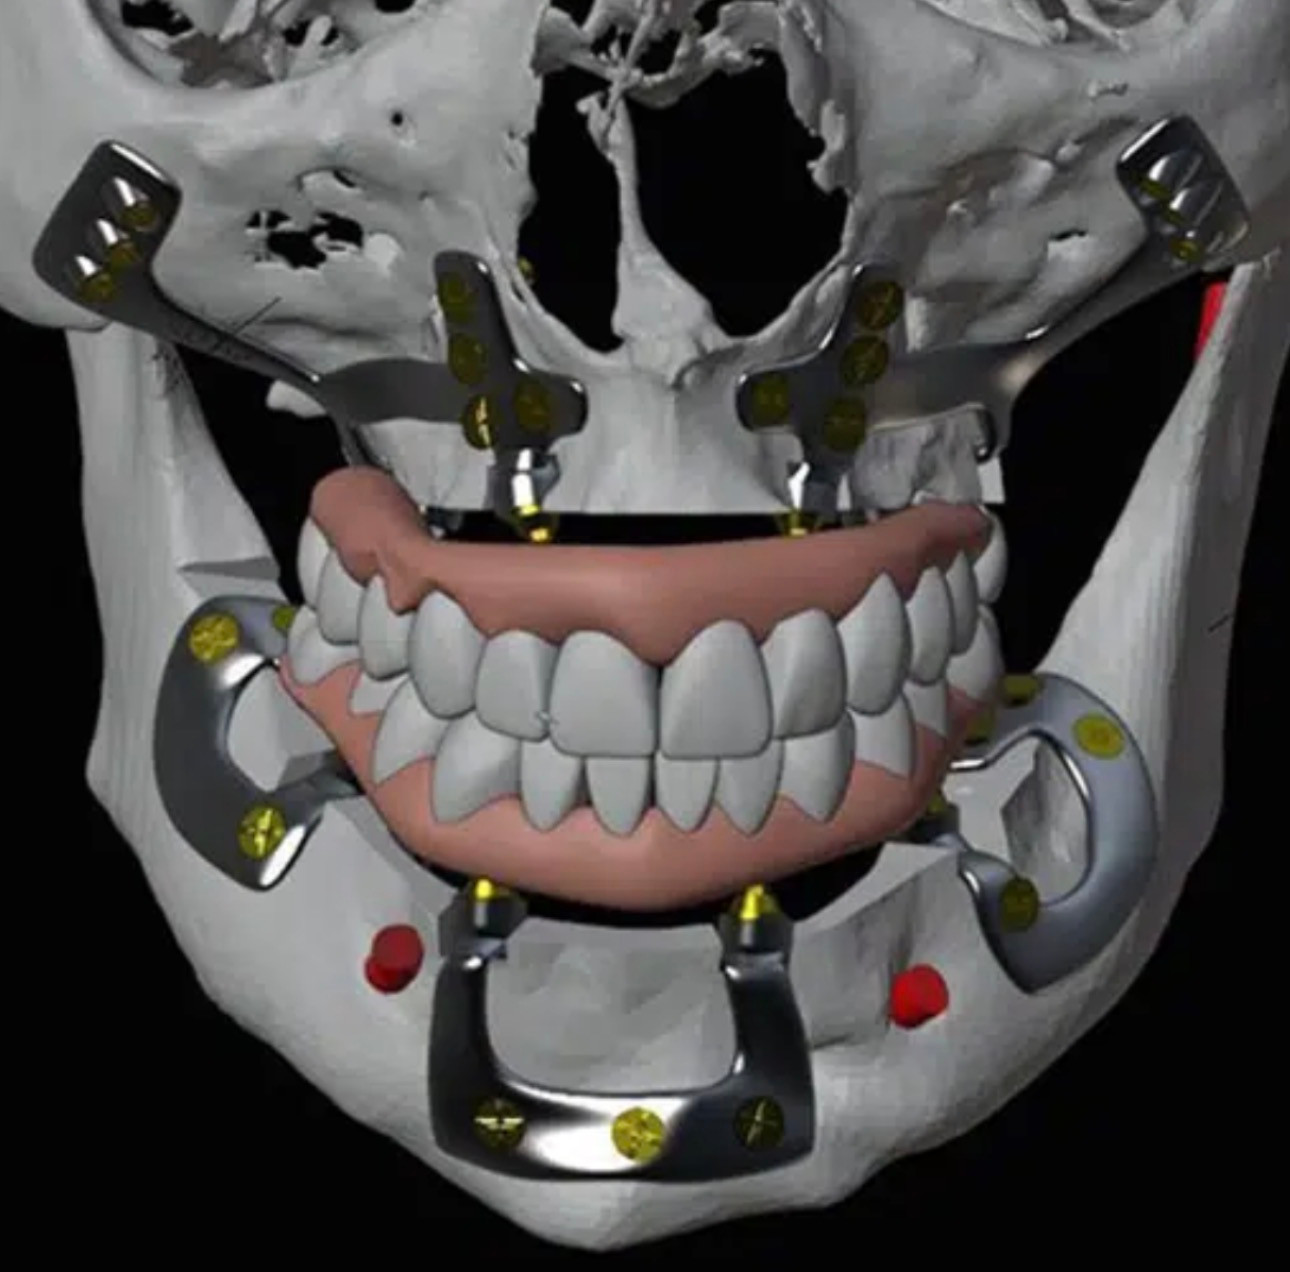

NOVO EQUIPAMENTO DE C.B.C.T., TAC 3D

A clínica de medicina dentária Dr. Ricardo Cruz dispõe de um exame radiológico de elevada precisão, através do novíssimo equipamento de C.B.C.T., TAC 3D, o que permite realizar diagnósticos radiológicos com máximo rigor, através da tecnologia 3D, dando assim mais um importante passo tecnológico na elevada qualidade e segurança que oferece aos seus pacientes, na área da Cirurgia Oral e Implantologia.

IMPLANTOLOGIA

Visa reabilitar a falta de um ou mais dentes através da colocação de implantes dentários.